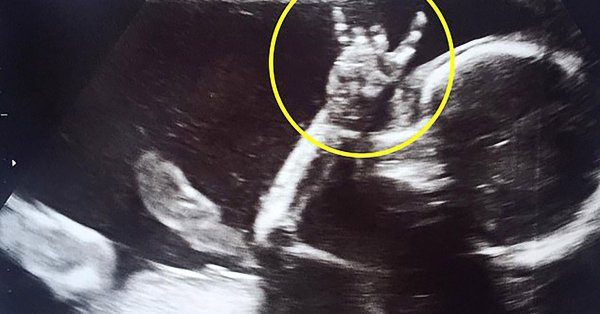

Đến khi đi siêu âm thai, bé gái trong bụng cô Jodie thực sự mang đến cho họ một bất ngờ lớn.

Cụ thể, khi hai vợ chồng đến bệnh viện để siêu âm tuần thứ 24 thai kỳ, vì em bé luôn quay mặt vào trong, cô Jodie liền nhẹ nhàng nói: "Con có thể cho cha mẹ nhìn thấy con một chút không, để cha mẹ chắc chắn rằng con vẫn đang ổn..."

Thật bất ngờ, khi cô Jodie vừa nói xong, em bé trong bụng cô lập tức giơ tay lên, làm biểu tượng hệt như các ngôi sao nhạc Rock hay làm, khiến tất cả mọi người vừa thích thú vừa vui sướng.